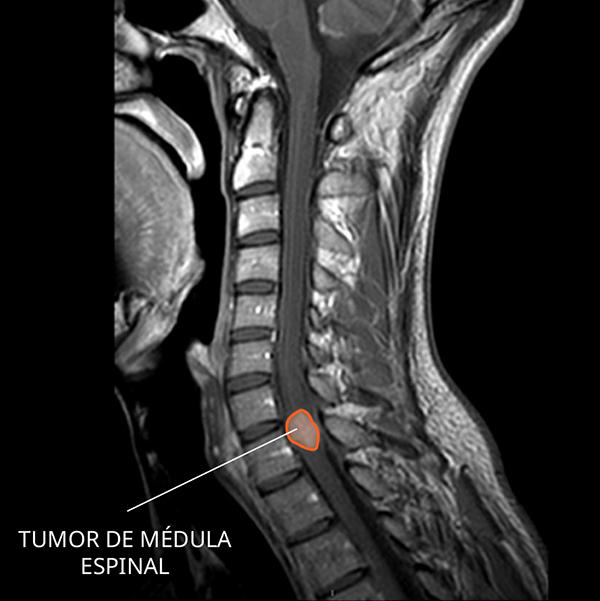

Imagen por resonancia magnética (IRM) de un ependimoma en la médula espinal.

Fuente: NCI-CONNECT

¿Cómo se ve un ependimoma en las imágenes por resonancia magnética?

El ependimoma se suele ver como una masa bien definida que se vuelve brillante con el contraste.